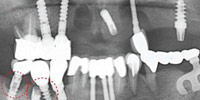

可选方法:种植牙(单颗缺失、多颗缺失及多各牙缺失)、All-on-4种植牙(半/全口牙缺失)、烤瓷牙(个别牙缺失)、活动义齿(全部牙缺失类型)

种植牙(单颗缺失、多颗缺失及多各牙缺失)

All-on-4种植牙(半/全口牙缺失)

烤瓷牙(个别牙缺失)

活动义齿(全部牙缺失类型)